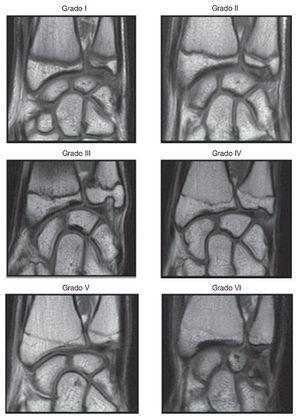

Para la lectura de imágenes se siguieron las recomendaciones descritas en investigaciones previas5,6. Los lectores (2 radiólogos y un médico de medicina deportiva) efectuaron una evaluación ciega, en cuanto a la información básica sobre los participantes. Los resultados se presentaron en un formato preestablecido y en un sobre cerrado, que solo incluía una descripción del código asignado, el grado de fusión y la firma. Cada imagen fue leída de manera independiente y en distintos momentos por cada evaluador. El grado de fusión fue la clasificación más común entre los 3 resultados de los evaluadores (tabla 1) (fig. 1).

Figura 1. Imágenes que muestran el grado de fusión ósea de la epífisis distal del radio visto mediante imágenes de resonancia magnética de la epífisis distal del radio.

De acuerdo con las observaciones realizadas por los investigadores y teniendo en cuenta los resultados de estudios previos11, la MO en el fútbol se puede dividir en grados o etapas para dar homogeneidad a la competición y evitar dificultades de la EC. A partir de la clasificación en 6 categorías del grado de fusión de la EDRI por RM propuesta en estudios previos5,6, se propuso la reestratificación en 3 categorías en función de las etapas de la MO: fase de madurez A o inmaduros (grado i de fusión), etapa de madurez B o en desarrollo (grados de fusión ii-iv) y etapa de madurez C o maduros (grados de fusión v y vi) (tabla 1). El 10% de las imágenes fueron seleccionadas aleatoriamente y reevaluadas por uno de los lectores para evaluar la correlación intraobservador por test-retest.